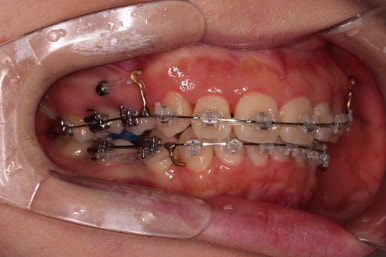

부산무턱교정치과 초진 시 입안의 모습입니다.

전반적으로 치열이 삐뚤고요. 아랫니가 윗니보다 뒤쪽으로 많이 가려져 있죠.

그래서 앞에서 봤을 때 아래 앞니가 거의 보이지 않는 상태인데요.

이런 교합을 "과개교합"이라고 표현합니다.

전반적인 교합, 치열, 과개교합, 튀어나와 보이는 앞니 등을 개선해줘야겠네요.

장치를 부착합니다.

이번 환자분이 선택한 장치는 엠파워 클리어라고 하는 자가결찰 세라믹 장치인데요.

철사를 묶는(결찰) cap이 장치에(자가) 달려있는 장치 중에 세라믹 성분으로 되어 심미성이 우수한 브라켓입니다.

우선은 적응을 위해서 윗니만 장치를 부착하고요.

아랫니는 과개교합 개선을 위해 앞니 먼저 시작합니다.

아래 앞니는 깊숙하게 솟구쳐 오른 치아를 밑으로 끌어내리기 위해 미니스크류를 식립하게 됩니다.